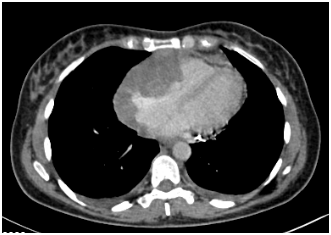

A 55-year-old African American woman presented with a one-month history of progressive exertional dyspnea and chest tightness. She had no significant past medical history. An echocardiogram revealed a large pericardial effusion and features of cardiac tamponade. A cardiac CT scan (Figure 1A) showed a mass at the pericardium extending into the right ventricular myocardium. Multiple bilateral lung nodules were noted with the largest measuring 1.6 cm in diameter.

A pericardial catheter was placed and a large bloody effusion was drained. A cardiac MRI (Figure 1B) revealed a 10 cm infiltrating soft tissue mass involving the right atrium and right ventricle. The right coronary artery was encased and attenuated. The mass extended into the atrioventricular groove and infiltrated the roof of the right ventricle. The anterior surface of the aortic root was also encased. Heterogeneous enhancement of the mass suggested a vascular lesion suggestive of angiosarcoma.